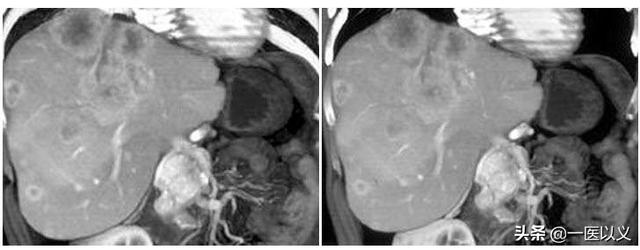

Die meisten kavernösen Hämangiome werden zufällig bei der körperlichen Untersuchung per Ultraschall entdeckt. Typische Läsionen haben charakteristischere Bilder auf Ultraschall, CT und MR, und eine qualitative Diagnose ist nicht schwierig. Bei der Ultraschall- und CT-Anreicherung sind sie typischerweise "early out and late in", und beim MR-Scan T2 ist ein "Glühbirnenzeichen" zu erkennen (siehe unten).

Ein hepatisches Hämangiom ist nicht dasselbe wie eine Leberzyste. Eine Leberzyste ist ein Wassersack, während ein Hämangiom, wie der Name schon sagt, eine Blutlache ist, die mit Blut und nicht mit Wasser gefüllt ist. Hepatische Hämangiom hat typische Merkmale auf CT-Anreicherung, 95% der Läsionen können durch CT oder Magnetresonanz-Anreicherung diagnostiziert werden, muss Hämangiom tun Anreicherung, um die Diagnose zu bestätigen Oh.